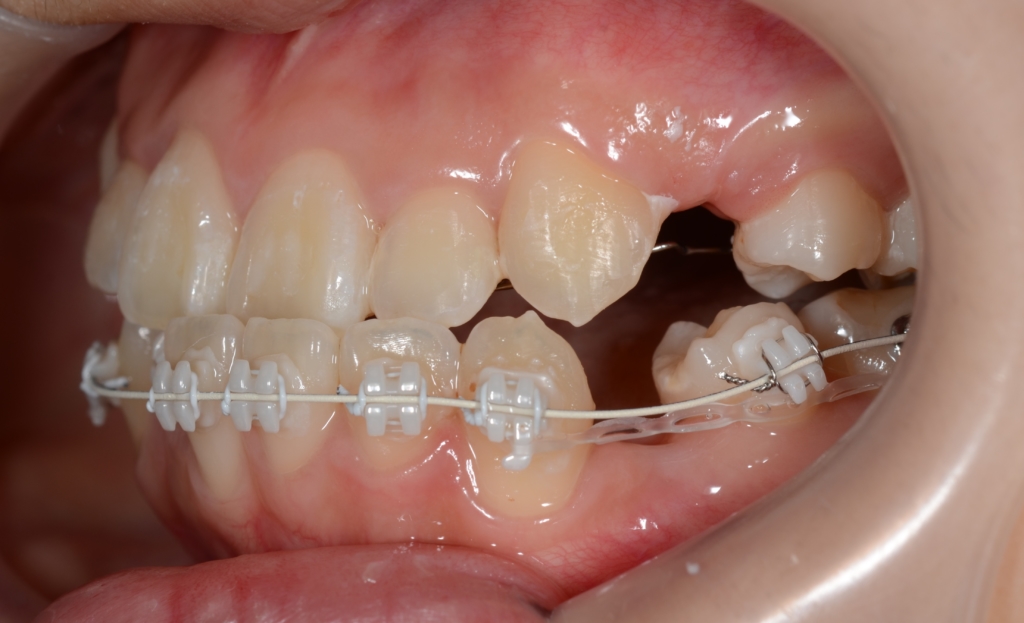

マルチブラケットシステム(ハーフリンガル type)で矯正を開始。

途中、早期の被蓋改善を図るため、上の奥歯から下の前歯へ引っ掛ける顎間ゴムを3か月間使用しています。

【1年経過】

【残る隙間を閉じて仕上げへ】